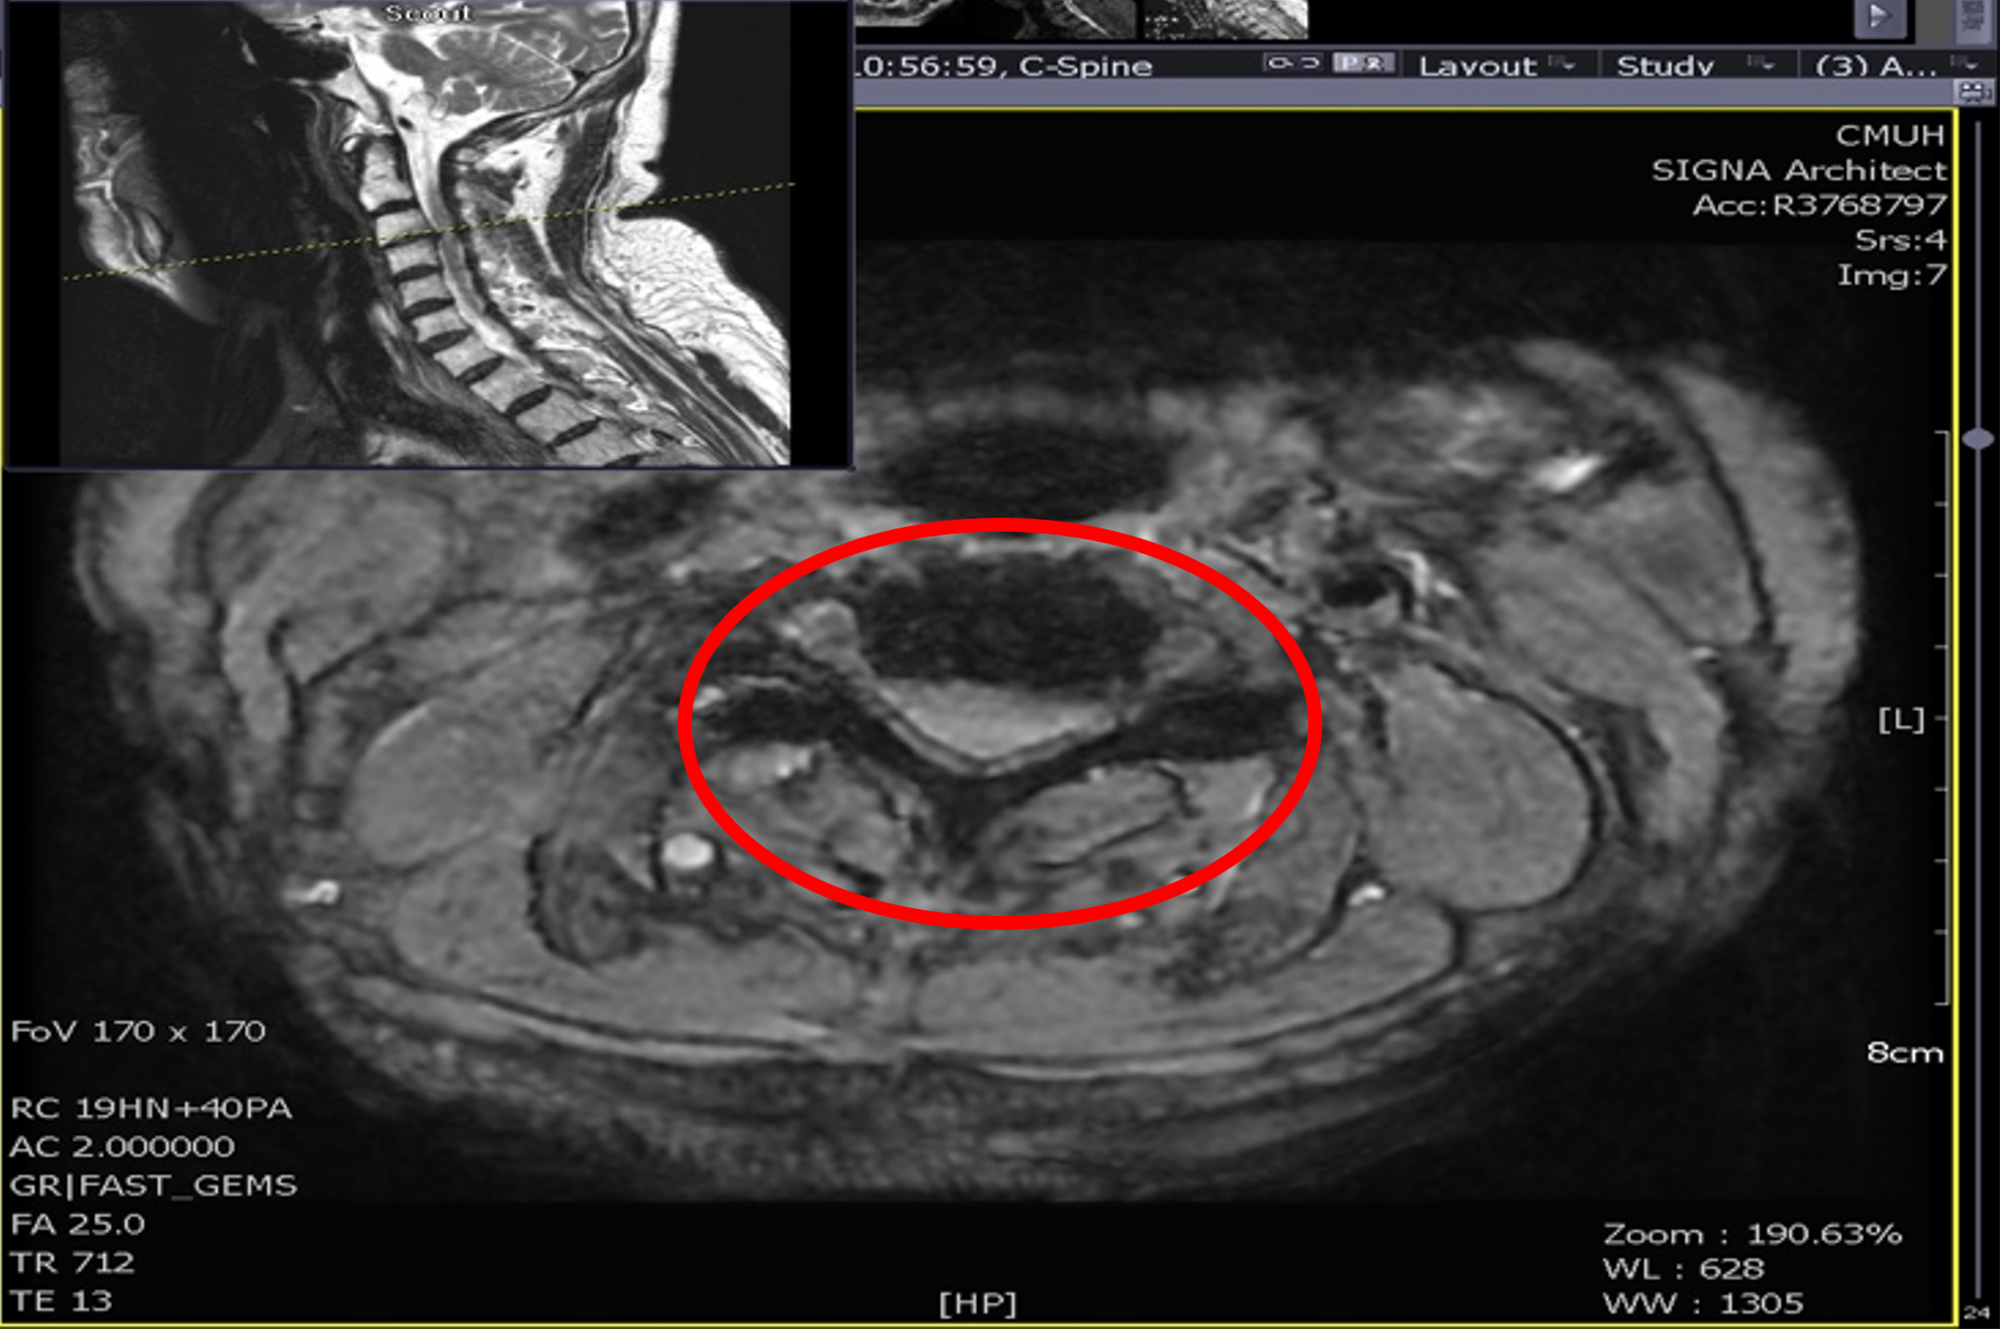

陳肇烜主任說明,患者就診時雙手明顯麻痛,右手完全無法舉起,雙腿僅能微弱抬起,已需依賴輪椅代步。影像檢查顯示其頸椎第3至第4節因外傷性椎間盤突出,造成脊髓壓迫嚴重。考量患者合併多重慢性病及長期使用抗凝血藥,手術與麻醉風險極高,若延遲治療恐導致永久性癱瘓。醫療團隊在手術前即啟動跨科整合照護,包含暫停抗凝血藥、進行心臟超音波檢查及新陳代謝科會診,確保病患在安全狀態下接受手術。

圖一:正常頸椎(上圖)應可看到完整灰色脊髓與白色腦脊髓液。病人受傷之頸椎第3/4節(上方下圖),無法看到正常脊髓與腦脊髓液。